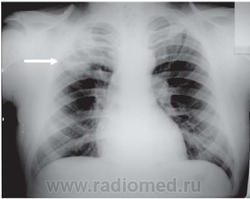

Родококкоз, как правило, встречается у лошадей и жеребят. Человек родококкозом не болеет. Но, у пациентов со СПИДом родококкоз встречается, и описано значительное количество случаев с легочными изменениями, вплоть до "кавитаций".